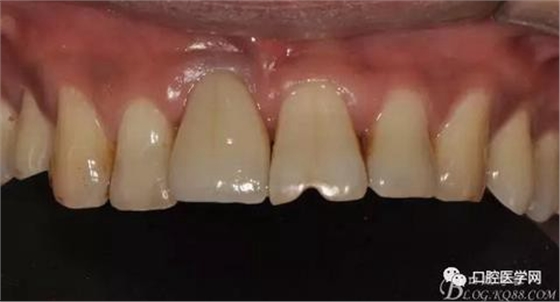

圖21 術后正位照

圖22 術后正位黑背板照

圖23 術后正位咬頜照